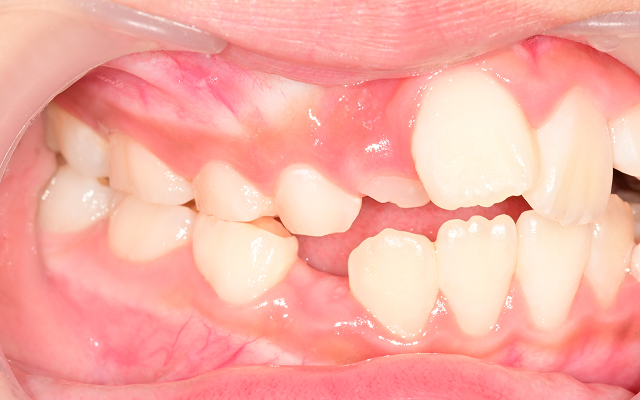

턱뼈의 성장이 비대칭으로 진행되어 성인 교정 시 수술이 필요할 수도 있음(양악수술)

교합 불균형으로 턱관절 통증, 비대칭 얼굴선이 생길 수 있음